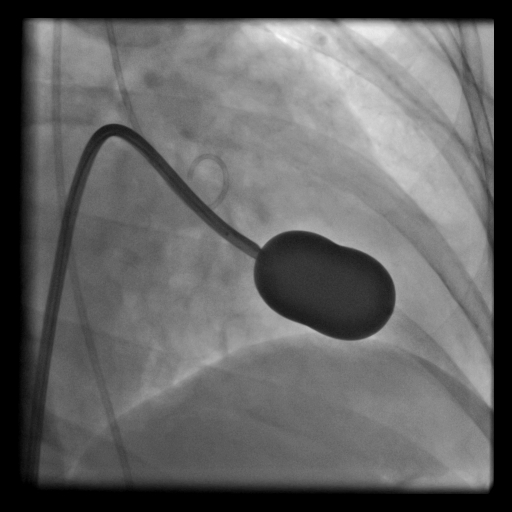

Romatizmal kalp hastalığına bağlı mitral kapakta darlık gelişebilir ve bu tablo ciddi nefes darlığına, AF gibi ritm bozukluğuna, felç ve sağ kalp yetmezliğine ve AC ödemine yol açabilir. Hastanın bu sıkıntıları yaşamadan kapağın ya ameliyatla değiştirilmesi ya da mitral balon işlemi ile ameliyatsız açılması gerekir. Mitral balon işlemi, daralmış mitral kapağın kasıktan girilerek ilerletilen balon ile açılması işlemidir, ameliyat değildir, yaklaşık yarım saat süren bir işlemdir.

- Mitral Kapak Darlıklarında Balon Tedavisi